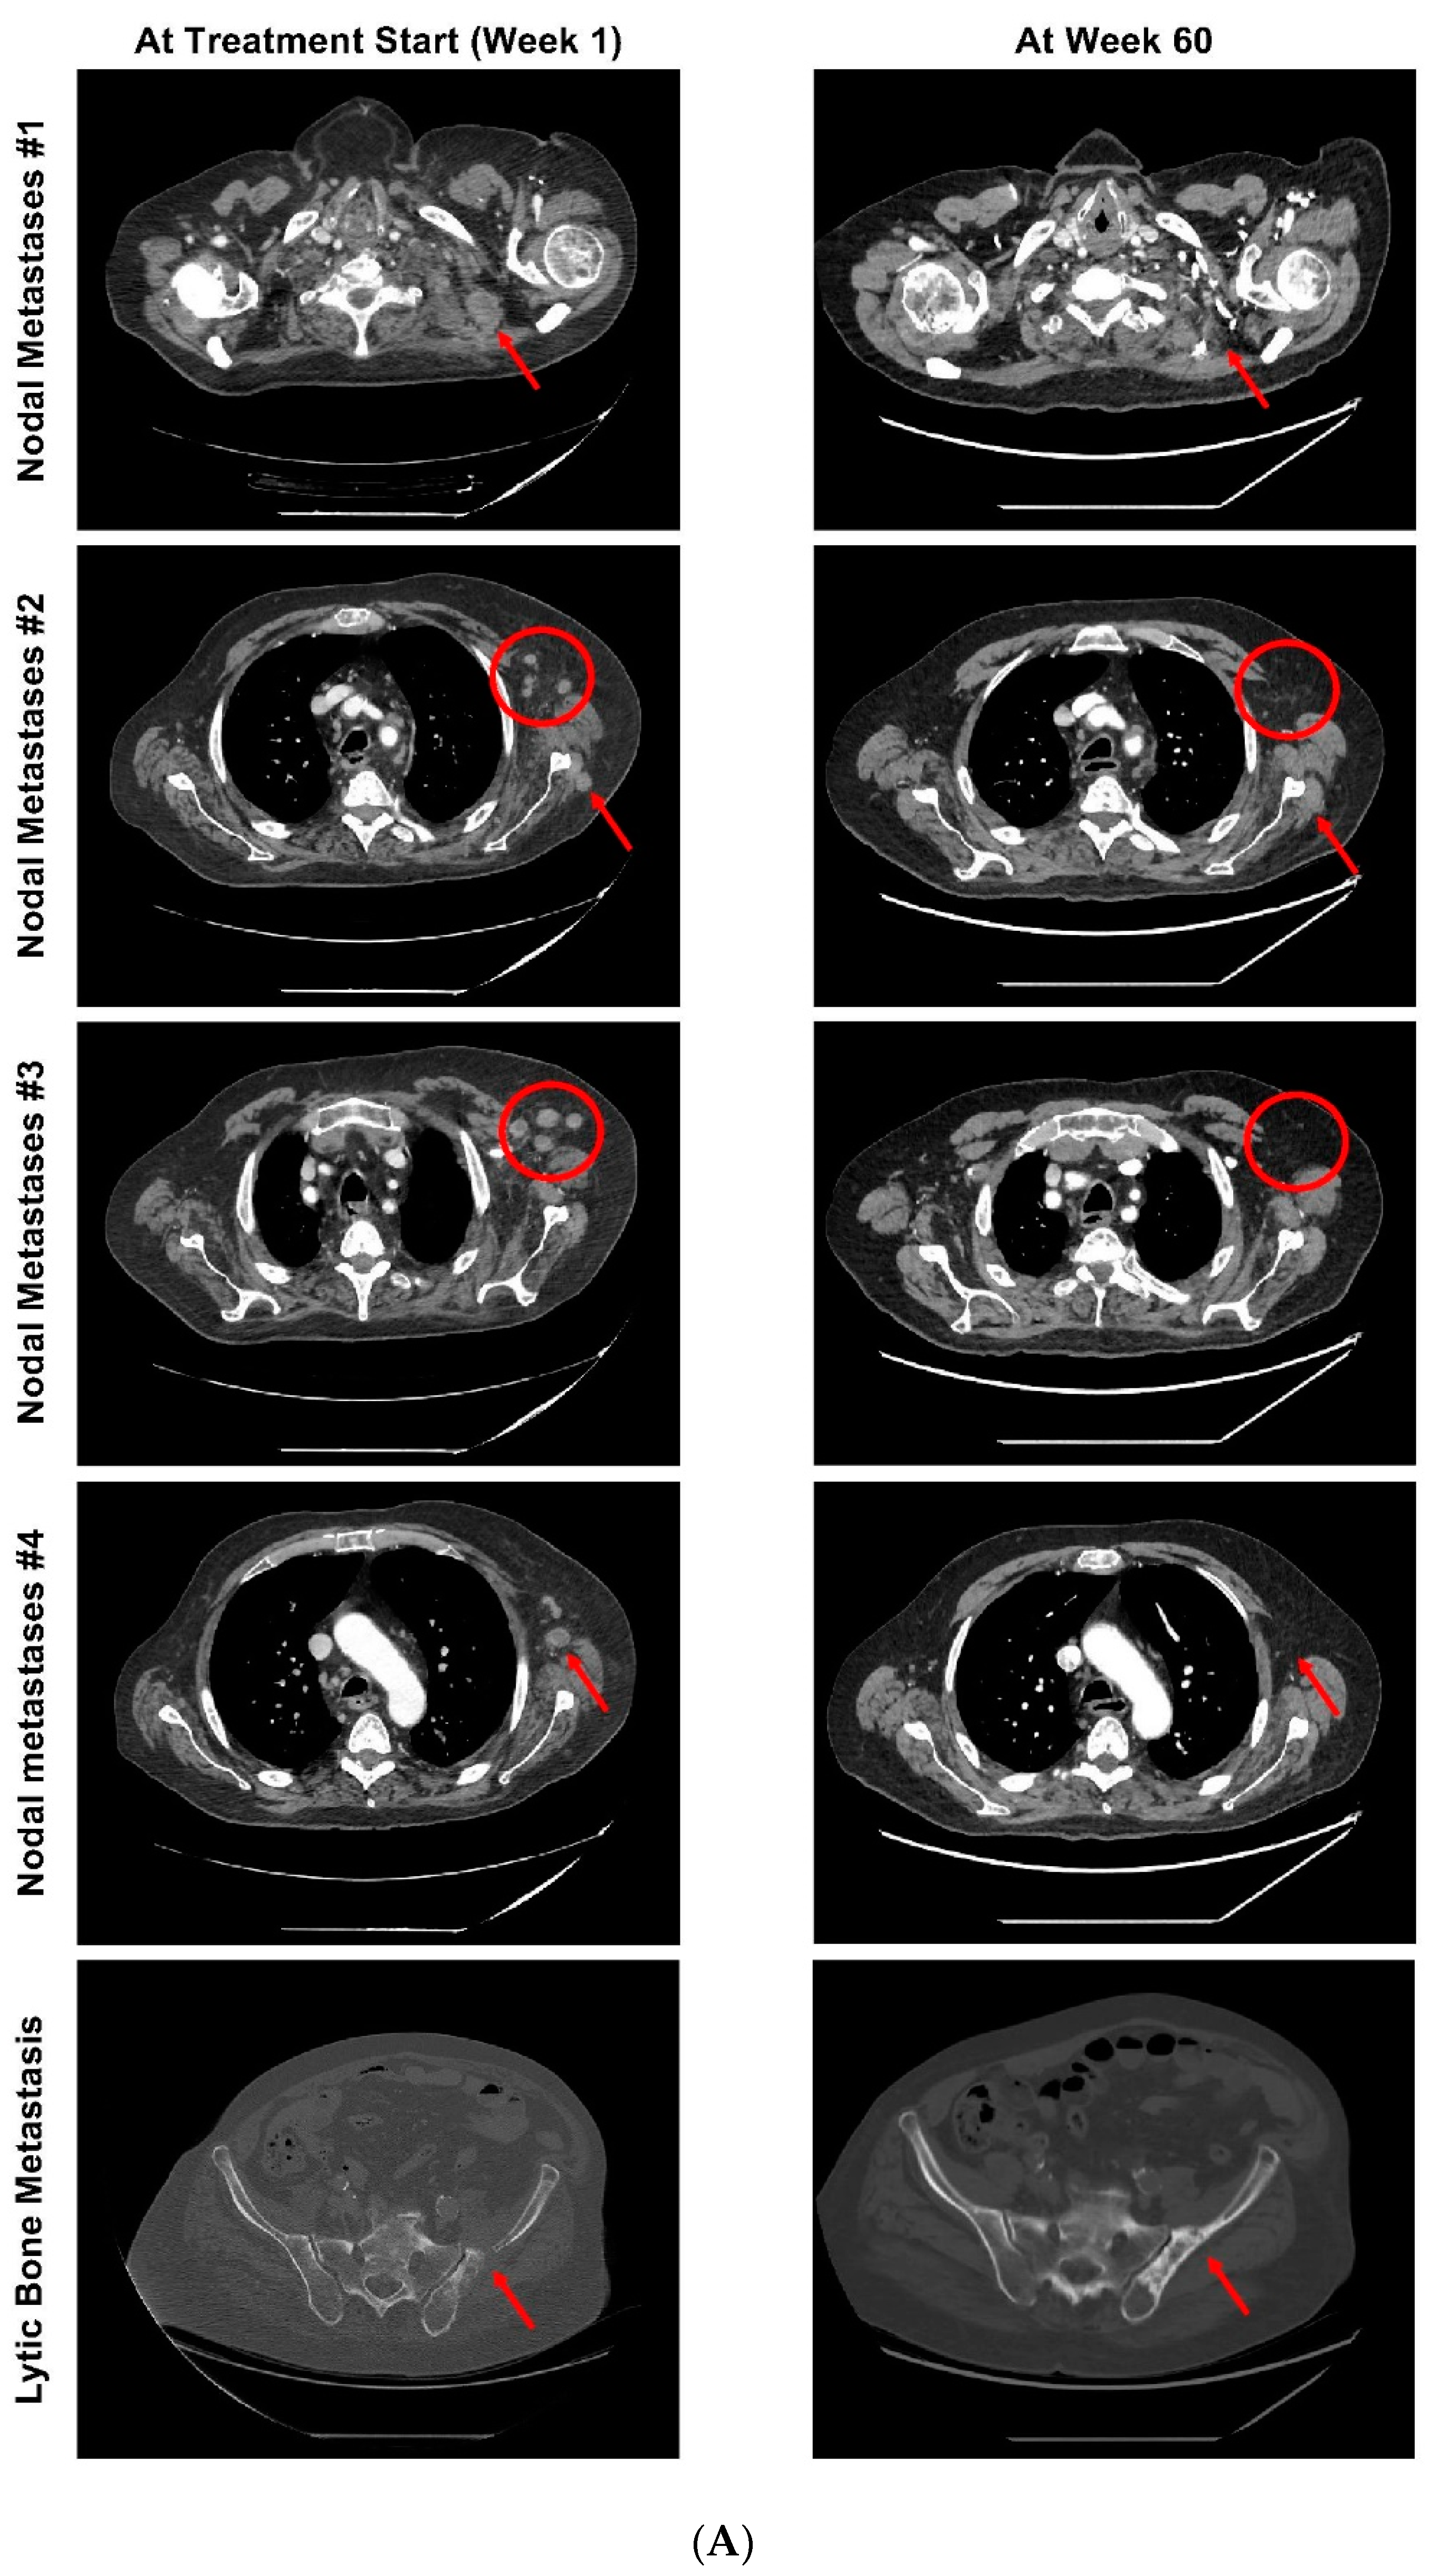

2. Case Report